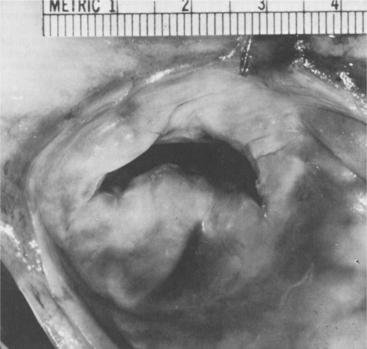

Regardless of the underlying cause, dilated cardiomyopathy results from extensively damaged myocardial muscle fibers and is characterized by cardiac enlargement. The heart ejects blood less efficiently than normal, so that a large volume of blood remains in the left ventricle after systole, which results in ventricular dilation with enlargement and dilation of all four chambers and eventually leads to CHF (Figs. 12-16 and 12-17).

Figure 12-16 A, Cross-sectional view of dilated cardiomyopathy. B, Hypertrophied heart. (From Kinney M: Comprehensive cardiac care, ed 7, St Louis, 1991, Mosby, pp 346, 349.)

Figure 12-17 Gross pathologic specimens of the cardiomyopathies. A, Hypertrophic cardiomyopathy, showing a marked increase in myocardial mass and preferential hypertrophy of the interventricular septum. B, Normal heart, with normal left ventricular dimensions and thickness. C, Dilated cardiomyopathy, showing marked increase in chamber size. Atrial enlargement is also evident in both cardiomyopathies (A and C). (From Seidman JG, Seidman C: The genetic basis for cardiomyopathy: from mutation identification to mechanistic paradigms, Cell 104:557, 2001.)

Hypertrophic cardiomyopathy is distinguished by inappropriate and excessive left ventricular hypertrophy (thickening of the interventricular septum) and normal or even enhanced cardiac muscle contractile function. Over time, the overgrowth of the wall leads to rigidity in the myocardium. The result is decreased diastolic functioning, since the rigid myocardium cannot relax during the diastolic phase, reducing the amount of blood flowing into the ventricles. Restrictive cardiomyopathy is the least common form; it is identified by marked endocardial scarring (fibrosis) of the ventricles, and the resulting rigidity impairs diastolic filling.